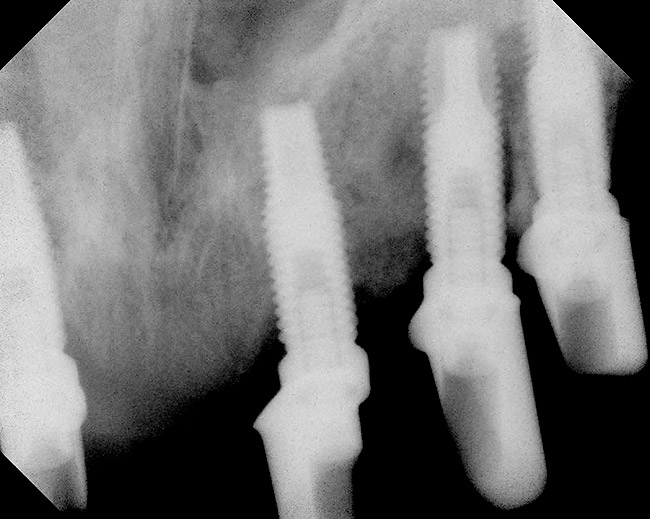

Figure 9  Laboratory occlusal view of four implant analogs with internal implant-abutment connections in a mandibular master cast. The posterior analogs replicate 5-mm diameter implant restorative platforms; the anterior analogs replicate 4.1-mm diameter implant restorative platforms.

Figure 9